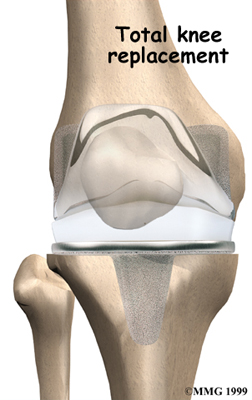

Artificial Knee Replacement

An artificial knee replacement is the ultimate solution for advanced knee OA.

Surgeons prefer not to put a new knee joint in patients younger than 60. This is because younger patients are generally more active and might put too much stress on the joint, causing it to loosen or even crack. A revision surgery to replace a damaged prosthesis is harder to do, has more possible complications, and is usually less successful than a first-time joint replacement surgery.

Related Document: FYZICAL Sprayberry's Guide to Artificial Joint Replacement of the Knee